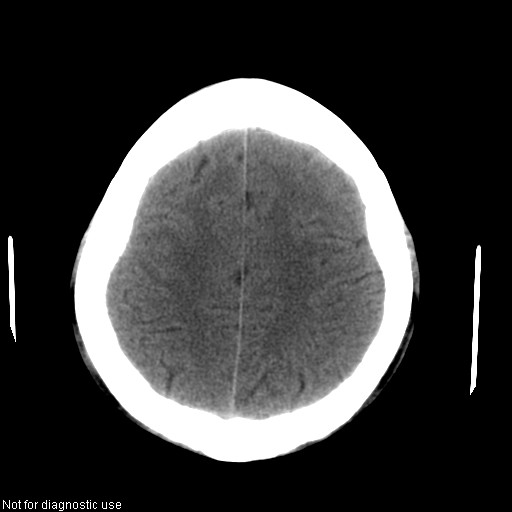

以下是引用hhcckk在2008-1-26 16:03:00的发言:[br]考虑病毒感染可能性大[br]1、病人发病时间短,1周,转移病灶时间长[br]2、楼主虽然没有告诉我们年龄,但从颅内情况来看,病人年纪不会很大,脑池,脑沟不是很明显,当然,可能有脑肿胀的原因,转移灶病人年纪一般较大[br]3、从病灶特点来看,转移多发生在灰白质交界区,多有指状水肿,占位效应明显,此病人呈对称性发布,发生在脑实质深部,与转移有所区别[br]4、病人经抗炎,止咳效果不好,可能是病毒感染,抗生素治疗效果不好[br]5、建议楼主1、增强 2、有呼吸系统的症状何不拍个胸片